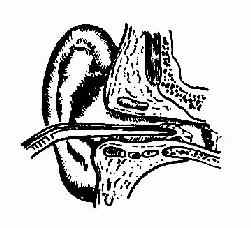

(三)活动的昆虫类可先滴入油剂、酒精或乙醚使其死后用镊、钩或冲洗取出(图11-2)。

| 图11-1 外耳道异物钩出法 | 图11-2 外耳道异物镊取法 |